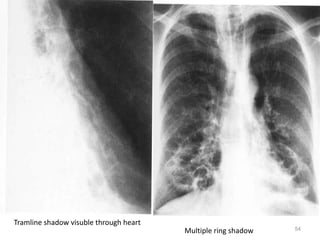

• X ray photo

Multiple ring shadow

Tramline shadow visuble through heart